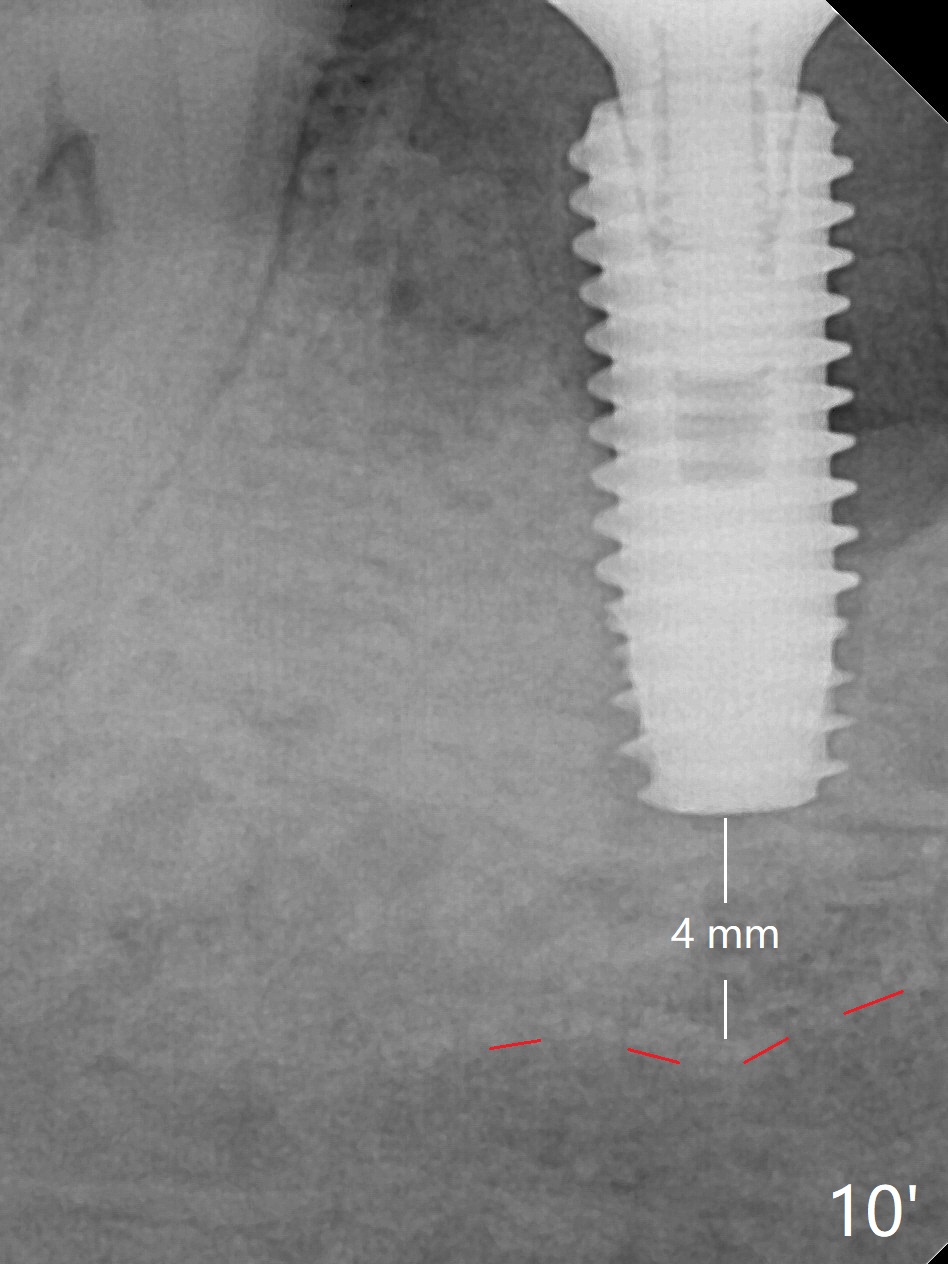

Preop oral Amoxicillin seems to be associated with reduction in the buccal and lingual (Fig.3 arrow) fistulae at #30, but there is mesiobuccal swelling (Fig.1 *) with 7 mm pocket (Fig.2). Osteotomy is initiated in the middle of the septum (Fig.3-5 S). As the osteotomy increases, it shifts mesially (Fig.6 arrow). Guided surgery is able to reduce shifting. A 5x13 mm implant is not seated completely (Fig.7) apparently due to osteotomy shifting. After removal of the bone from the osteotomy distally, the implant remains unseated with lower torque value (Fig.8). Following reuse of the 4.3 mm drill deeper by 1-2 mm, the implant is seated to a satisfactory depth (Fig.9 with increase in torque to 50 Ncm) with placement of Vera Graft (*) and a 7.5x4(3) mm abutment. After a second round of allograft placement (Fig.10 *), the implant is found to be 4 mm from the IAC. At the later stage of osteotomy, the coronal end of the septum is destroyed with loss of osteotomy depth landmark. It is apparent that the soft tissue landmark may be more reliable. The implant threads appear to be covered by the bone graft 3.5 months postop (Fig.11). The abutment is changed to 6.5x5(3) mm one before impression with minor margin prep. The bone density seems to increase 5 months postop, i.e., immediately post cementation (Fig.12) and 10 months postop (5 months post cementation (after retightening abutment), Fig.13 (*)). Periimplantitis develops mesiobuccally, consistent with bone loss 1 year 7 months post cementation (Fig.14 *); the implant seems to have been buccally placed. Bone graft is necessary with PRF or GEM21S if the vein is small and 6-month membrane with a hole around a 7.5x4(4) cemented abutment for easy wound closure. Take 5x5 CM CBCT to determine which wall has defect, buccal or lingual. Check mesial contact. If so, remove the crown, reseat the abutment (possible incomplete seating) and re-impress after bone graft.